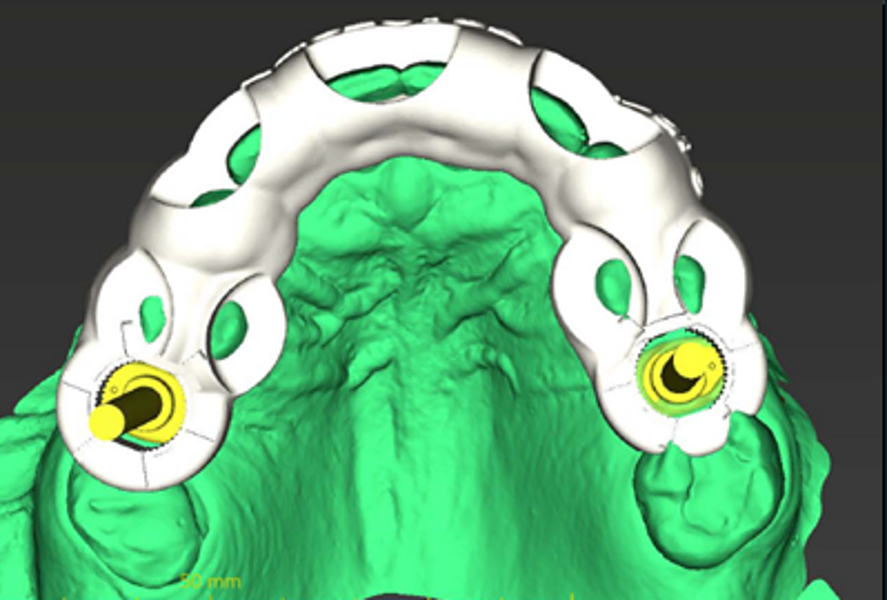

The patient’s maxillary and mandibular arches were scanned using the Straumann SIRIOS system. The scans, along with the DICOM files from the CBCT scan, were sent via Straumann AXS to Smile in a Box (Straumann) for treatment planning, surgical guide design and 3D printing of the model and surgical guides (Figs. 4, 5a–f & Figs. 6a–d).

After evaluation and validation of the plan, it was decided for site #15—where a residual root was present and the bone density was generally soft—that a Straumann BLX (Roxolid, SLActive, regular base) 4.5 × 8.0 mm implant would be placed, along with an M shape Straumann Anatomic Healing Abutment XC (regular base/wide base; gingival height: 1.5 mm). For site #25, extraction of the remaining root was planned and would be followed by the placement of a Straumann BLC (Roxolid, SLActive, regular base) 3.75 × 8.00 mm implant. This narrower site had a visible lamina dura, favourable for achieving primary stability. An M shape Straumann Anatomic Healing Abutment XC (regular base/wide base; gingival height: 1.5 mm) was also selected for this site to support proper soft-tissue emergence during the 60- to 90-day healing period. Owing to the expected post-extraction gaps between the implants and buccal bone walls, cerabone plus (botiss biomaterials) was planned to be used for grafting.